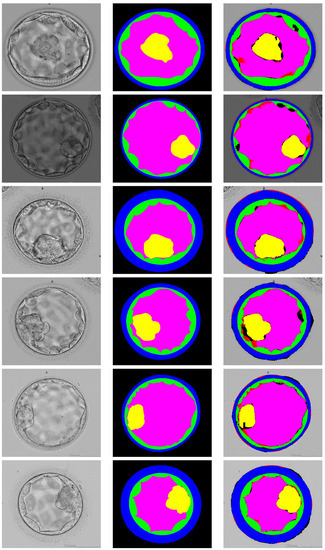

4.3. Comparison with State-of-the-Art

| Method | ICM | BC | TE | ZP | Background | Mean Jaccard | Parameters |

|---|---|---|---|---|---|---|---|

| U-Net baseline [35] | 79.03 | 79.41 | 75.06 | 79.32 | 94.04 | 81.37 | 31.03 M |

| TernausNet [38] | 77.58 | 78.61 | 76.16 | 80.24 | 94.50 | 81.42 | 10.0 M |

| PSP-Net [39] | 78.28 | 79.26 | 74.83 | 80.57 | 94.60 | 81.51 | 35 M |

| DeepLab-V3 [40] | 80.60 | 78.35 | 73.98 | 80.84 | 94.49 | 81.65 | 40.0 M |

| Blast-Net [31] | 81.07 | 80.79 | 76.52 | 81.15 | 94.74 | 82.85 | 25.0 M |

| ECS-Net (Proposed) | 85.26 | 88.41 | 78.43 | 85.34 | 94.87 | 86.46 | 2.83 M |